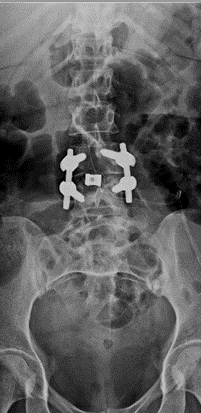

32 years old lady presented with worsening back pain for 4 weeks duration following elective caeseran section done for malpresentation. There was history of repeated attempts of puncture for spinal anaesthesia . She was cathetrised which was removed on day 2 and she has received intravenous broad spectrum antibiotics for 5 days duration. Her surgical wound healed well with no documentation of fever, abdominal pain, cough, dysuria or discharge per vaginum. At presentation her pain was predominantly in lower lumbar region ( VAS – 9/10) with severe paraspinal muscle spasm. She was not able to sit for few minutes and had difficulty in turning in bed . she couldn’t nurse her child due to pain with inability to assume comfortable postures. Root tension signs were negative with no neurological deficits. Radiographs revealed L3/4 disc space reduction with end plate changes. Hematological evaluation showed  elevated TLC, ESR,CRP ( Table 1) . Septic screening for urine , blood and chest infection was negative. MRI showed evidence of spondylodiscitis at L3/4 (FIG 5,6) . She underwent CT guided biopsy which was negative. She later underwent PLIF L3/4 and had grown pseudomonas from the necrotic disc material sent for culture & sensitivity. She was mobilized on day -1 with lumbo sacral brace. Her low back pain reduced significantly ( VAS -2/10) and she needed minimal analgesics ( single dose of intravenous paracetamol ) for one week.  She had 2 weeks of intra venous Cefaperazone + sulbactum followed by 4 weeks of oral antibiotics. Radiographs showed fusion by 3 months ( FIG 7,8) and hematological parameters normalized by 6 weeks.(Table 1)

Fig 7: L3/4 PLIF – AP view

Fig 8: L3/4 PLIF- Lateral view